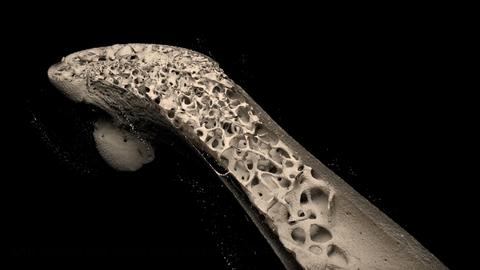

New type of bone cell could reveal targets for osteoporosis treatment

Using intravital imaging of living bone tissue, researchers identified a new type of bone cell – osteomorphs – which fuse together to form osteoclasts, which help break down and recycle old parts of the skeleton. The study identified that the osteomorphs have a unique genomic profile separate to osteoclasts, revealing promising and as yet unexplored targets for therapy for a number of skeletal diseases.